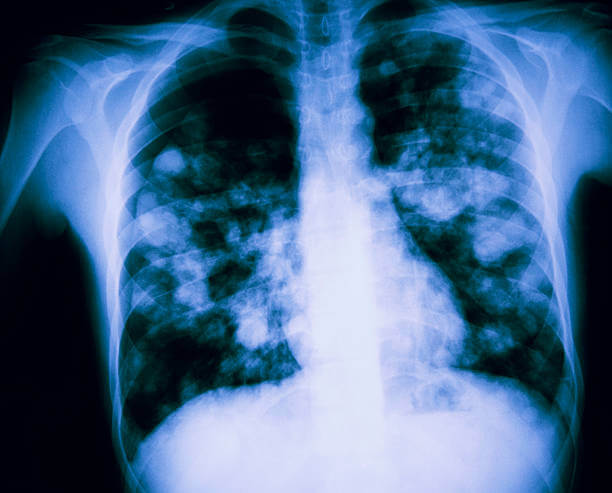

합병증 확인: 폐부종과 관련된 합병증 여부를 확인하기 위해 흉부 X-선, CT 스캔, 혈액검사 등이 수행될 수 있습니다. 이는 폐 이외의 다른 기관과 조직의 상태를 확인하는데 도움을 줍니다.